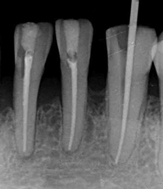

コラム「やむを得ず神経を取り除く」の画像